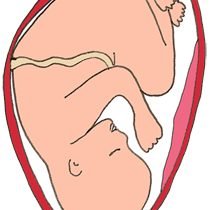

Nel corso di tutta la gravidanza, i recettori tattili si distribuiscono su tutto il corpo del bambino. Il quinto mese è, però, il mese dell’esplosione dei sensi. Il feto scopre, infatti, una parte dei 5 sensi: il tatto, l’odorato, il gusto, l’udito e per finire la vista, anche se i suoi occhi sono ancora chiusi.

continua>>> Il tatto